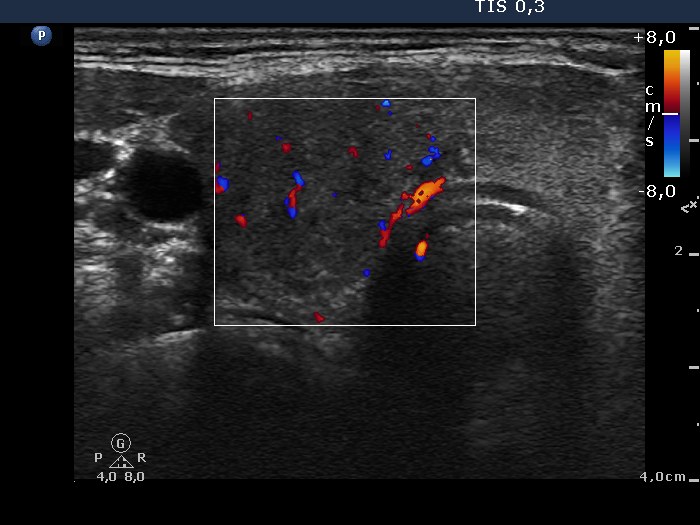

Ultrasonography: The right lobe was moderately hypoechogenic, while the left one was echonormal-minimally hypoechogenic. Several more hypoechogenic areas with ill-defined borders were found. The vascularization was decreased.